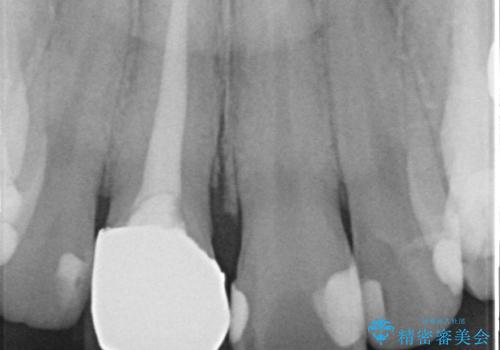

- 右上1の前歯の見た目が気になるので被せ物をやり替えたいといらっしゃった方の症例です。

再根管治療終了後、オールセラミッククラウン(スペシャル)によって隣在歯に合わせた補綴を行いました。